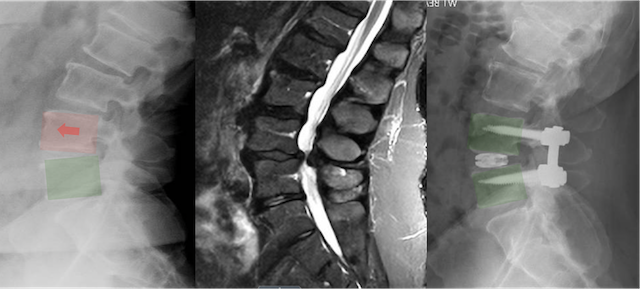

Medical images showing spinal imaging with disc replacement devices and spinal alignment.

How is TLIF surgery performed?

TLIF is performed through an incision (or two) in the lower back.

Typical steps include:

• A small portion of bone is removed to relieve nerve pressure

• The damaged disc is removed

• A spacer filled with bone graft is placed into the disc space

• Pedicle screws and rods are placed to stabilize the spine

These steps restore disc height, decompress nerves, and allow fusion to occur.